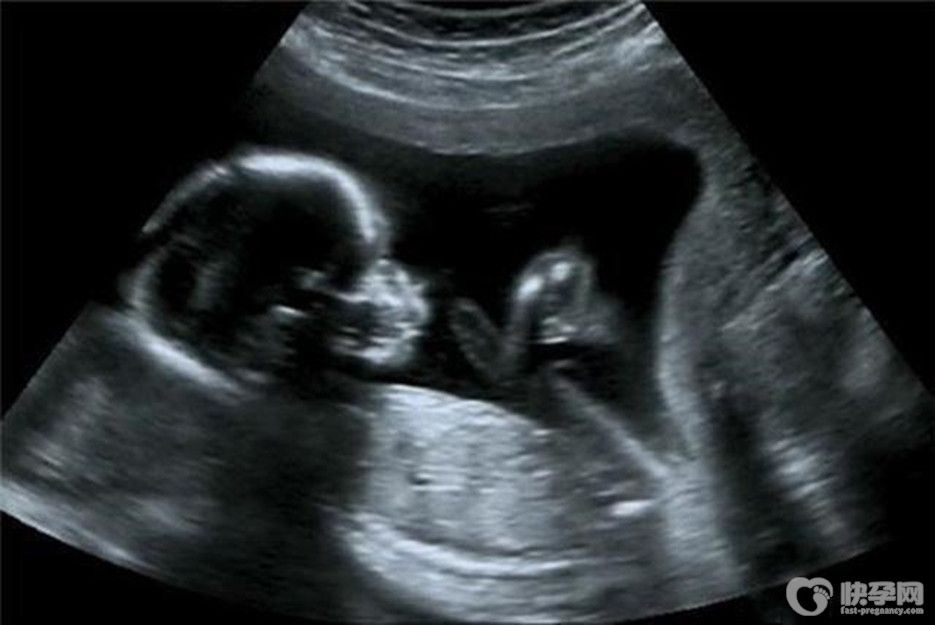

热点:b超对胎儿有影响吗?看看质深医生怎么说

对于孕妈妈们说,孕期中少了不b超的检查,有的孕妈妈认为b超有辐射,对胎宝宝有影响,因此就不想做b超检查,其实这种做法是不对的。今天我们就来聊聊b超对胎儿是否真有影响..